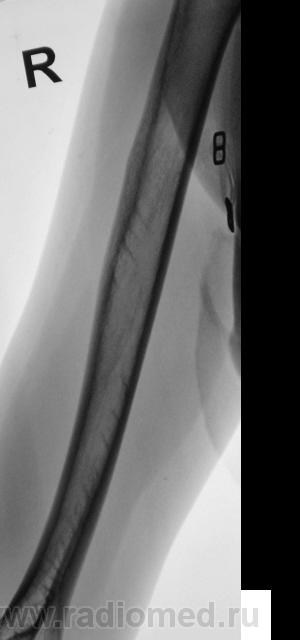

Пациентка направлена врачом хирургом на рентгенографию правой плечевой кости. Пациентка жалуется на боли в плече, как дневные, так и ночные, отмечает, что эти боли усиливаются при физической нагрузке. Из "разговора" выяснено, что боли резко усилились в течение последних двух месяцев. Пациентка отмечает, что боли усиливаются при физической нагрузке. Выяснено, что 1,5 года тому был удар (упала), в то место, которое болит. Что посоветуете, уважаемые коллеги?

Боковая проекция добавлена.

Изображения в прямой проекции с увеличением.

Мне кажется, есть локальная слоистость кортикального слоя. Надо бы спросить ту, имя которой я поклялся не упоминать.

Неоднозначно всё